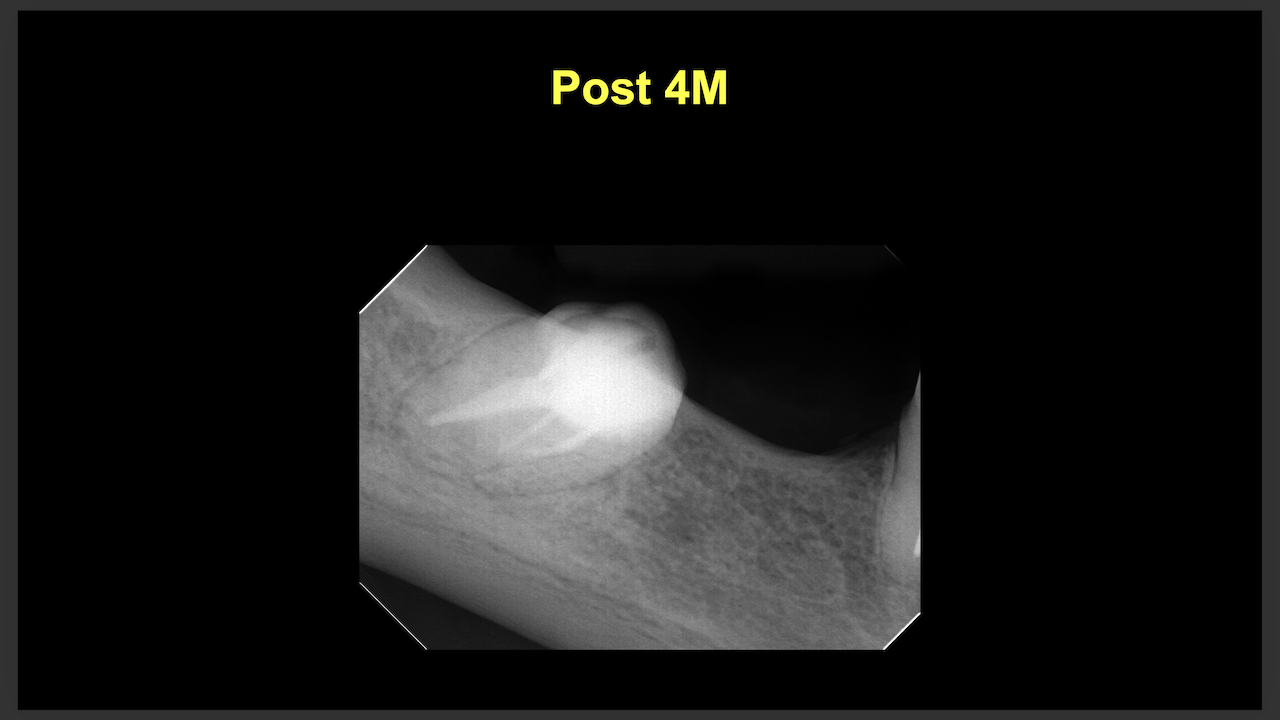

次はN先生と同一法人のF先生。

#10のRCTと3M recallである。

#9,10と病変があるが、

#9はColdに2秒で反応し、その痛みが5秒でおさまったことから生活歯と判断し、

Cold, EPTに反応がなく打診痛もある#10を患歯と考え、#10のみ根管治療することとなった。

その際の成功率は86%である。

と術前に患者さんに告げて治療へ導入し以下のようになった。

3ヶ月しか経過していないが根尖病変は大きく減少した。

治療していない#9には変化があまりないがだからと言って手をつける必要性はない。

患者に症状がないからだ。